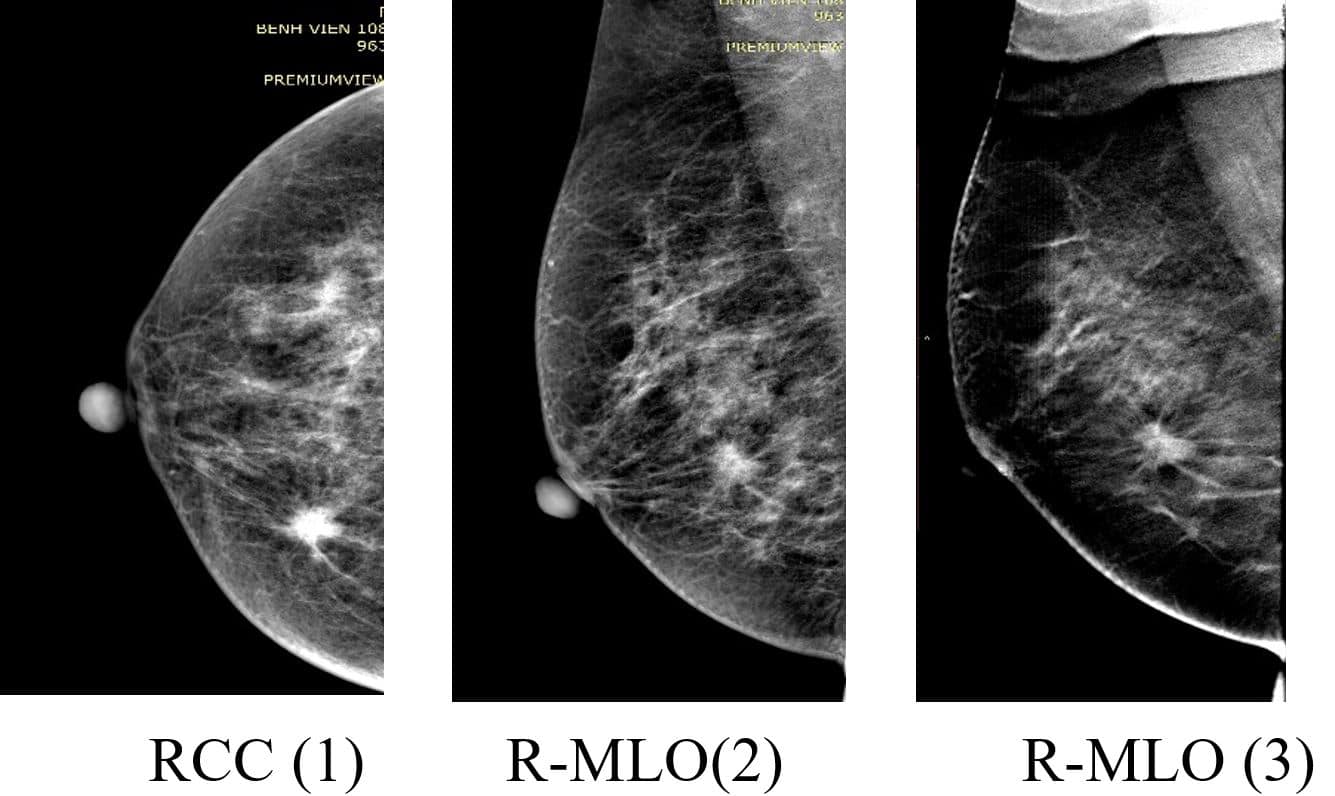

Chụp Nhũ ảnh là phương pháp chẩn đoán hình ảnh chuyên sâu dành cho tuyến vú, sử dụng tia X liều thấp để tạo ra hình ảnh rõ nét về cấu trúc bên trong vú. Đây là kỹ thuật hàng đầu trong việc tầm soát, phát hiện sớm các tổn thương vú và ung thư vú ngay cả khi chưa có triệu chứng lâm sàng.

Phát hiện u vú lành tính và ác tính

Đánh giá u cục, vôi hóa, biến đổi mô tuyến vú